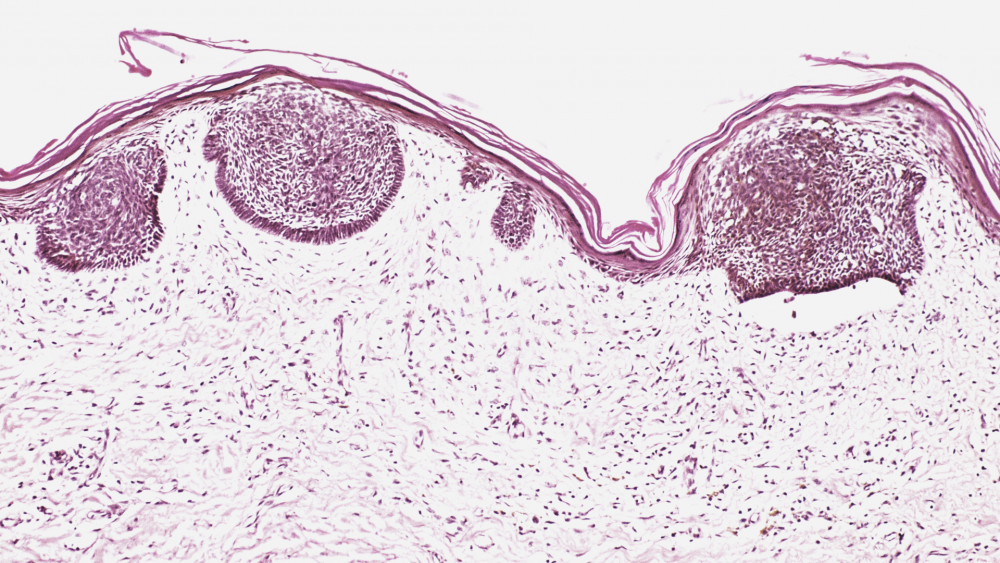

Рак губы

Рак губы — злокачественное новообразование, образованное из клеток многослойного плоского эпителия в зоне красной каймы губ.